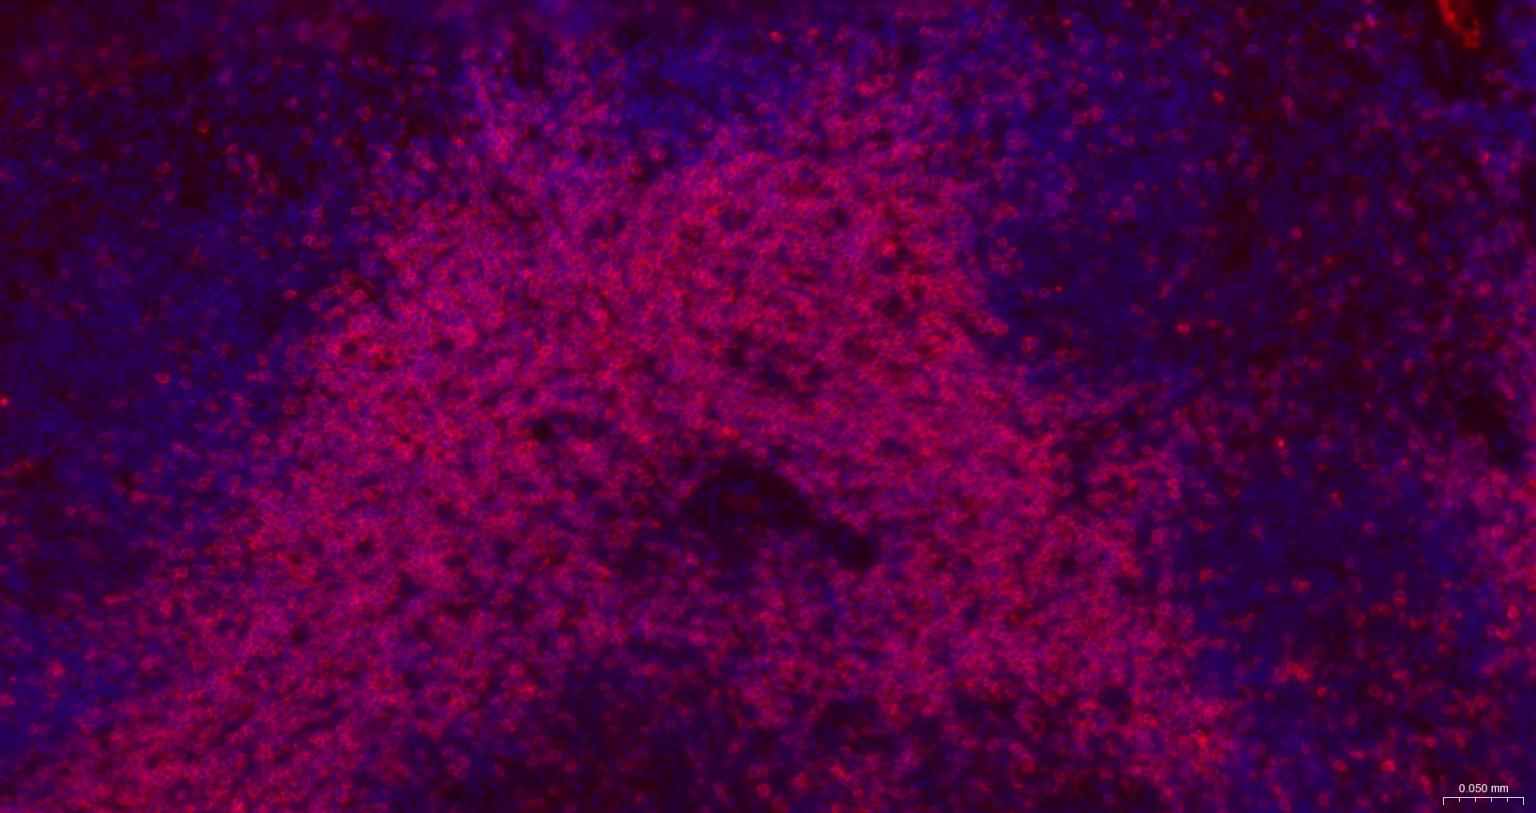

Paraformaldehyde-fixed, paraffin embedded Mouse Spleen; Antigen retrieval by boiling in sodium citrate buffer (pH6.0) for 15 min; The section was incubated with CD3E Monoclonal Antibody, Unconjugated (bsm-60002) at 1:500 overnight at 4°C. Followed by conjugated Goat Anti-Rabbit IgG antibody (Red, bs-0295G-BF594), DAPI (blue, C02-04002) was used to stain the cell nuclei.